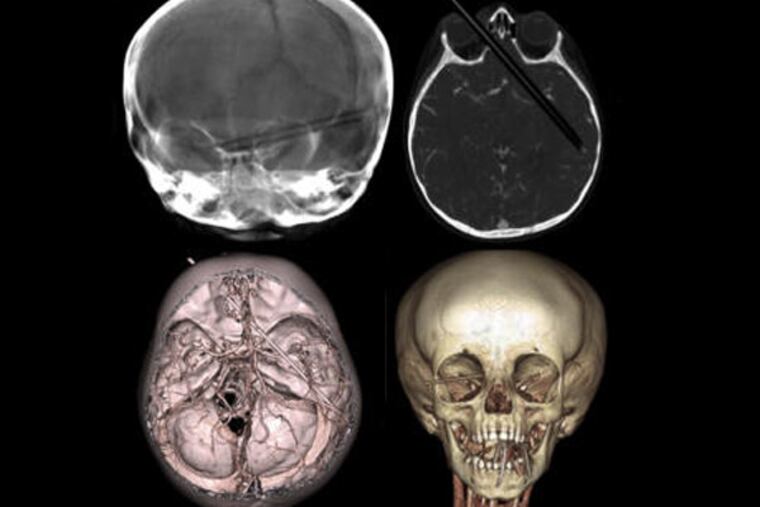

20-month-old Olivia Smith was coloring when she accidentally fell off the sofa in her home in New Boston, N.H. In the midst of the fall, one of her colored pencils entered her right eye socket, crossed through her brain and lodged itself there.

And unfortunately this colored pencil wasn't toddler-sized – the entire 5 inch instrument was lodged in her skull. Take a minute to process that – 5 whole inches. Yes I know what you're thinking, was there even that much room for the pencil? Apparently, yes.

Luckily (which is probably the understatement of the year), the pencil managed to take the one and only route through Olivia's brain that would not cause her serious and permanent damage. Even the angle in which the pencil entered managed to miss all major optical nerves – it's almost like it never even happened!

Dr. Darren B. Orbach, neurointerventional radiologist at Boston Children's Hospital, told CBS News that if he had to draw a line through a person's skull that would create the least amount of damage, it couldn't get any closer than that pencil's trajectory.